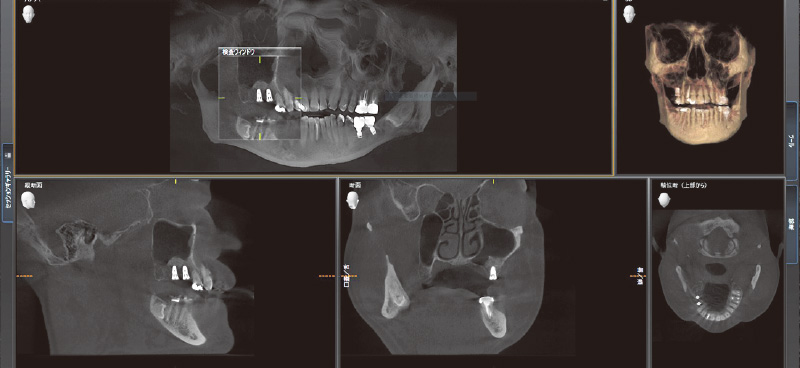

![[写真] CT画像よりサイナスリフト後、インプラント埋入を行うに十分な骨量が確保されている状態を確認できる](/academic/dentalmagazine/wp-content/uploads/sites/2/2025/11/195-10_photo03.jpg)

図3 CT画像よりサイナスリフト後、インプラント埋入を行うに十分な骨量が確保されている状態を確認できる。SPIインプラントシステムの特徴的なドリルは、シンプルで正確な埋入手術を可能としている。(デンツプライシロナ社製CTにて撮影) -